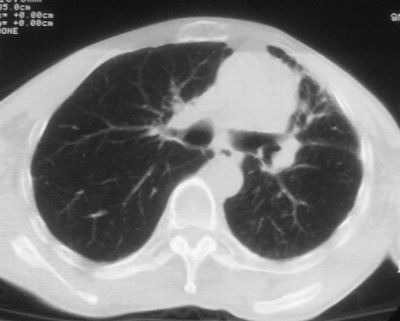

标题: CT11864:男,47岁,反复咳嗽、咯痰、咯血3年,请分析. [打印本页]

患者,男,47岁,反复咳嗽、咯痰、咯血3年,再发5天。痰培养未找到真菌、抗酸杆菌、癌细胞。

左肺上叶体积明显缩小,其内见多发透光区,纵隔向左侧移位,左肺下叶多发班片状病灶,边界模糊,1左肺上叶先天肺发育不全,2左肺下叶肺炎,

左肺上叶结核伴肺纤维化,纵隔移位,左肺下叶感染性病变,建议抗炎抗结核后复查,双肺气肿.

1)考虑为:左肺上叶肺结核(空洞形成),伴左下肺感染;不排除霉菌感染可能。2)肺气肿。

左肺上叶结核伴肺纤维化空洞形成并左肺下叶感染,纵隔牵拉移位,建议作进一步检查排除左侧肺霉菌感染可能。